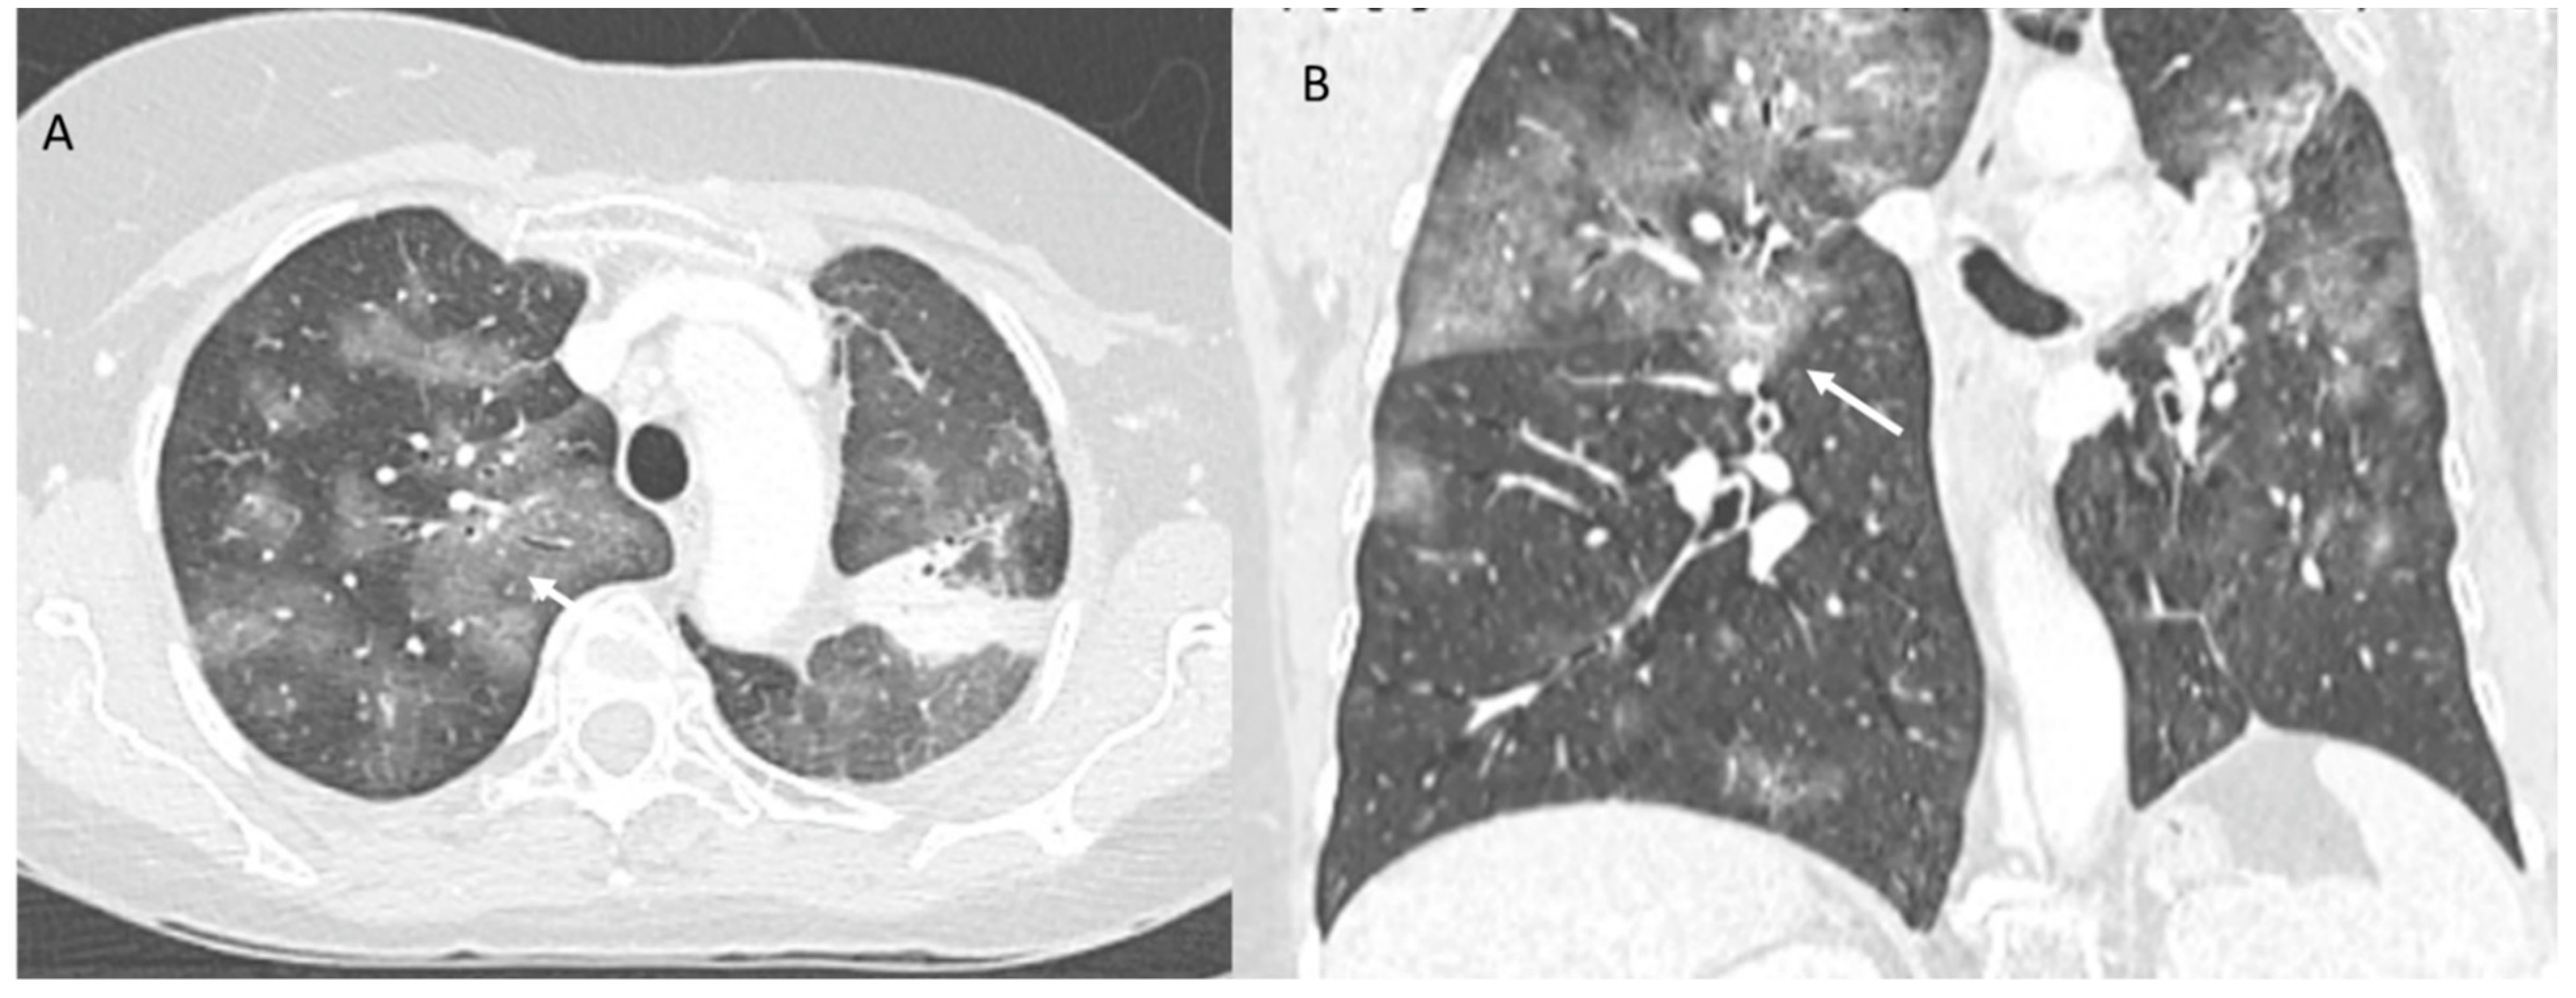

Acute interstitial pneumonia (AIP)–acute respiratory distress syndrome (ARDS) is not a model of ICI therapy-related pneumonia, although it is associated with a more severe clinical course and extensive pulmonary involvement with imaging. This pattern is characterized by geographic or diffuse ground-glass or consolidation opacities involving most, and sometimes all, of the lungs, although lobular sparing areas may be detected. There may also be a thickening of the interlobular septum and a “crazy pavement” pattern (Figure 3). The differential diagnosis is extensive and includes pulmonary oedema, haemorrhage, and infection. The findings of ARDS may also be due to extrapulmonary causes such as pancreatitis, sepsis and/or shock and transfusion reactions.

Figure 3. ICI-related pneumonitis. AIP-ARDS pattern on CT (axial: (A) and coronal: (B)): diffuse ground-glass opacities involving a majority of the lungs (arrows), although areas of lobular sparing can be detected.